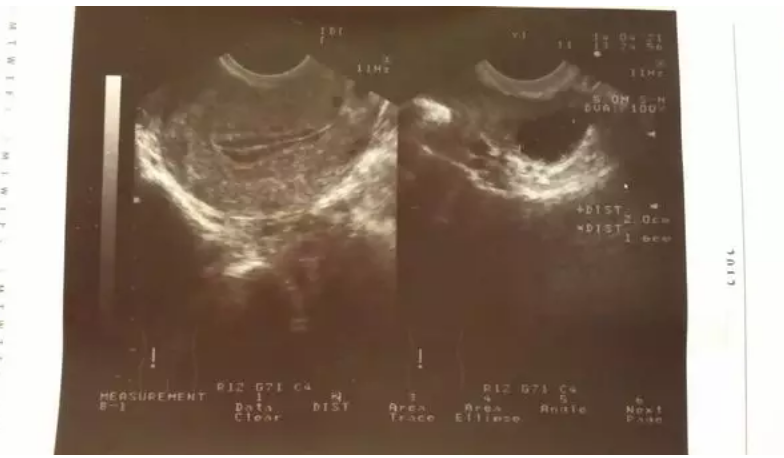

經(jīng)常有患者朋友問,“醫(yī)生,我內(nèi)膜太薄了,不能移植了,怎么辦呢?”或者是“別的醫(yī)生告訴我內(nèi)膜太薄,影響懷孕的?!? 這個(gè)問題有的時(shí)候還真是難以用簡(jiǎn)單的一句話來回答。今天我想和大家探討一下這個(gè)問題。 子宮內(nèi)膜的薄厚是怎么算的? 首先,子宮內(nèi)膜的厚與薄是有周期性的。 談到內(nèi)膜的厚或薄,最好說出是在月經(jīng)周期的第幾天。在女性一個(gè)月經(jīng)周期的起始階段即月經(jīng)期,子宮內(nèi)膜剛剛剝脫完全,即當(dāng)月經(jīng)期大量的月經(jīng)出血接近結(jié)束的時(shí)候,內(nèi)膜就應(yīng)該是很薄的,可以描述成線狀,即像一條線一樣薄,醫(yī)生會(huì)在病歷本上記錄內(nèi)膜呈“線狀”。 假如在月經(jīng)期接近結(jié)束的時(shí)候內(nèi)膜厚度仍然超過7mm,那么說明子宮內(nèi)膜剝脫不完全,反而是不正常的。一般情況下在月經(jīng)期大量經(jīng)血結(jié)束時(shí)最好是小于等于5mm。 然后,進(jìn)入卵泡發(fā)育期,卵巢內(nèi)的卵泡啟動(dòng)發(fā)育,隨著卵泡的不斷發(fā)育長大,會(huì)不斷分泌雌二醇,雌二醇主要作用于子宮內(nèi)膜,使子宮內(nèi)膜也不斷增厚,因此,子宮內(nèi)膜的增厚是伴隨卵泡發(fā)育而來的,一般情況下如果優(yōu)勢(shì)卵泡的直徑達(dá)到或超過15mm,子宮內(nèi)膜的厚度應(yīng)該在7-8mm或以上,正常女性此時(shí)子宮內(nèi)膜的厚度可以達(dá)到9mm左右。 所以子宮內(nèi)膜的厚度與卵泡的大小是緊密相關(guān)的,不能把兩者割裂開來。 下圖是優(yōu)勢(shì)卵泡直徑達(dá)到18mm時(shí)子宮內(nèi)膜的圖像,呈明顯三線征,中間的宮腔線回聲強(qiáng),上面的一條線以及下面一條線與宮腔線之間的組織呈低回聲。 舉個(gè)例子,某某,月經(jīng)周期第10天,卵巢呈多囊狀態(tài),雙側(cè)卵巢內(nèi)未見優(yōu)勢(shì)卵泡,此時(shí)子宮內(nèi)膜厚度是5mm,這種情況并不能說子宮內(nèi)膜是薄的,因?yàn)榇藭r(shí)沒有大卵泡存在,體內(nèi)沒有相應(yīng)的雌二醇產(chǎn)生,子宮內(nèi)膜當(dāng)然不會(huì)厚。 假如優(yōu)勢(shì)卵泡直徑達(dá)18mm,內(nèi)膜厚5mm,這種情況可以說子宮內(nèi)膜薄,肯定是有問題的。原因有很多,比如,口服過氯米芬(法地蘭),影響了子宮內(nèi)膜的增生,以及存在宮腔粘連導(dǎo)致內(nèi)膜增生障礙(流產(chǎn)清宮不當(dāng)可以發(fā)生宮腔粘連)。具體是什么原因需要結(jié)合B超具體分析。 除了薄厚,還要有好的形態(tài) 子宮內(nèi)膜除了厚與薄外,還有很重要的一點(diǎn):就是形態(tài)。 不是單純厚就好,還要有好的形態(tài)。好的子宮內(nèi)膜比較豐盈,有三條線,叫三線征,就像人的嘴巴。中間的一條線叫宮腔線,宮腔線最好從宮頸處連續(xù)上升至宮底,不要有中斷,有明顯的中斷通常是宮腔粘連的表現(xiàn),如下圖所示。 有的病人子宮內(nèi)膜回聲不均勻,在宮腔線和上下兩條線之間有一些點(diǎn)狀或片狀高回聲,有的病人在宮腔線處附近有明顯一團(tuán)高回聲,就是子宮內(nèi)膜息肉。以上所說的形態(tài)都是在晚卵泡期,就是優(yōu)勢(shì)卵泡接近16-18mm(接近排卵前)所出現(xiàn)的征象。 排卵后卵巢內(nèi)形成黃體產(chǎn)生孕激素,使子宮內(nèi)膜轉(zhuǎn)化為強(qiáng)回聲,所以內(nèi)膜的息肉及回聲不均勻就不容易觀察了。所以觀察子宮內(nèi)膜的好壞最好在晚卵泡期,即月經(jīng)周期第12天左右(假如月經(jīng)周期是28天左右的患者)。 如何保養(yǎng)子宮內(nèi)膜? 1、快走30分鐘,改善子宮血液循環(huán) 每天快步走30分鐘,子宮血液循環(huán)速度可提高10%。 2、每周游泳一次,提高宮縮能力 每周游泳2小時(shí),可使宮縮能力提高一成以上。養(yǎng)成游泳習(xí)慣,能提高宮縮能力,保持子宮內(nèi)溫度。 3、每周做3-4次“暖宮操” 方法是:雙膝自然分開,跪在墊子上,挺直腰部,向前彎腰,讓胸部盡量接近墊面,保持5分鐘。接著平躺在墊子上,做收腹提臀運(yùn)動(dòng),臀部在空中盡量保持3-5分鐘,感覺子宮隨身體一起收縮。 4、科學(xué)避孕 避孕套既能有效避孕,還能防止性傳播疾病感染子宮,讓子宮青春常在。一款優(yōu)秀的“口服避孕藥”不光能避孕,還能調(diào)節(jié)月經(jīng)周期。連續(xù)長時(shí)間服用同一種長效避孕藥,會(huì)讓調(diào)節(jié)體溫的神經(jīng)中樞產(chǎn)生鈍化反應(yīng),因此應(yīng)每年更換一種。 5、在排卵期親熱,溫暖子宮一整月 性高潮時(shí)出現(xiàn)的子宮痙攣對(duì)子宮有良性的刺激作用,它相當(dāng)于一次針對(duì)子宮的按摩。規(guī)律的性生活不僅能夠使男女雙方更加濃情蜜意,還能增加子宮血液循環(huán)。澳大利亞墨爾本大學(xué)的醫(yī)學(xué)研究專家發(fā)現(xiàn),在排卵期進(jìn)行一次美好的性生活,可讓子宮溫暖一整個(gè)月。 6、嚴(yán)防產(chǎn)后宮脫 產(chǎn)后不注意休息,經(jīng)常下蹲或干重活,增加腹壓,導(dǎo)致子宮沿著陰道向下移位,子宮可以從正常位置沿陰道下降子宮頸外口達(dá)坐骨棘水平以下,甚至子宮全部脫出于陰道口外,醫(yī)學(xué)上稱為子宮脫垂,簡(jiǎn)稱“宮脫”。 7、 高脂肪食物促進(jìn)了某些激素的生成和釋放,而子宮肌瘤的形成與大量雌激素刺激有關(guān),堅(jiān)持低脂肪飲食,要多喝水、按照最新推出的4+1金字塔膳食結(jié)構(gòu)來攝取必要的營養(yǎng)。忌食辛辣、酒類、冰凍等食品。